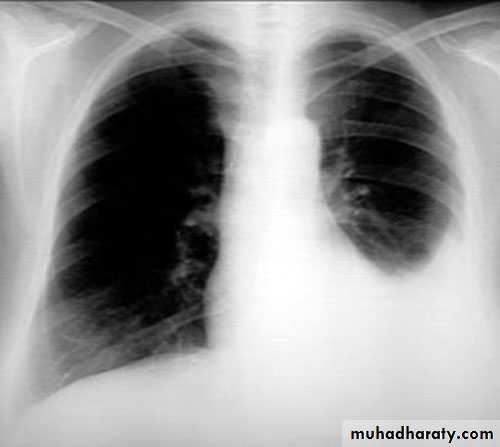

Massive pleural effusion